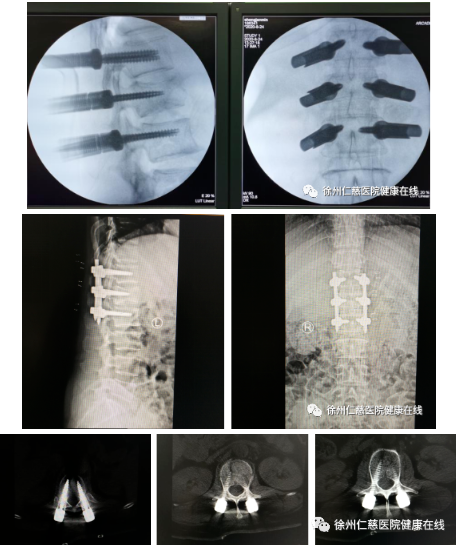

第二天,孟磊孙玉龙医生团队为患者进行了手术。术前,C型臂透视定位,调整机器人机器臂及标尺;术中,3D C型臂扫描,传送图像,根据扫描结果规划双侧椎弓根钉钉道入路,安装机器人导向器;沿导向器钻入导针至椎体后缘。透视导针位置良好,沿导针分别切开长约1.5厘米切口,开口攻丝后拧入空心长尾椎弓根螺钉,透视见定位准确,螺钉位置满意,安装螺帽,透视见骨折复位满意,内固定位置良好。术中出血仅20ml。